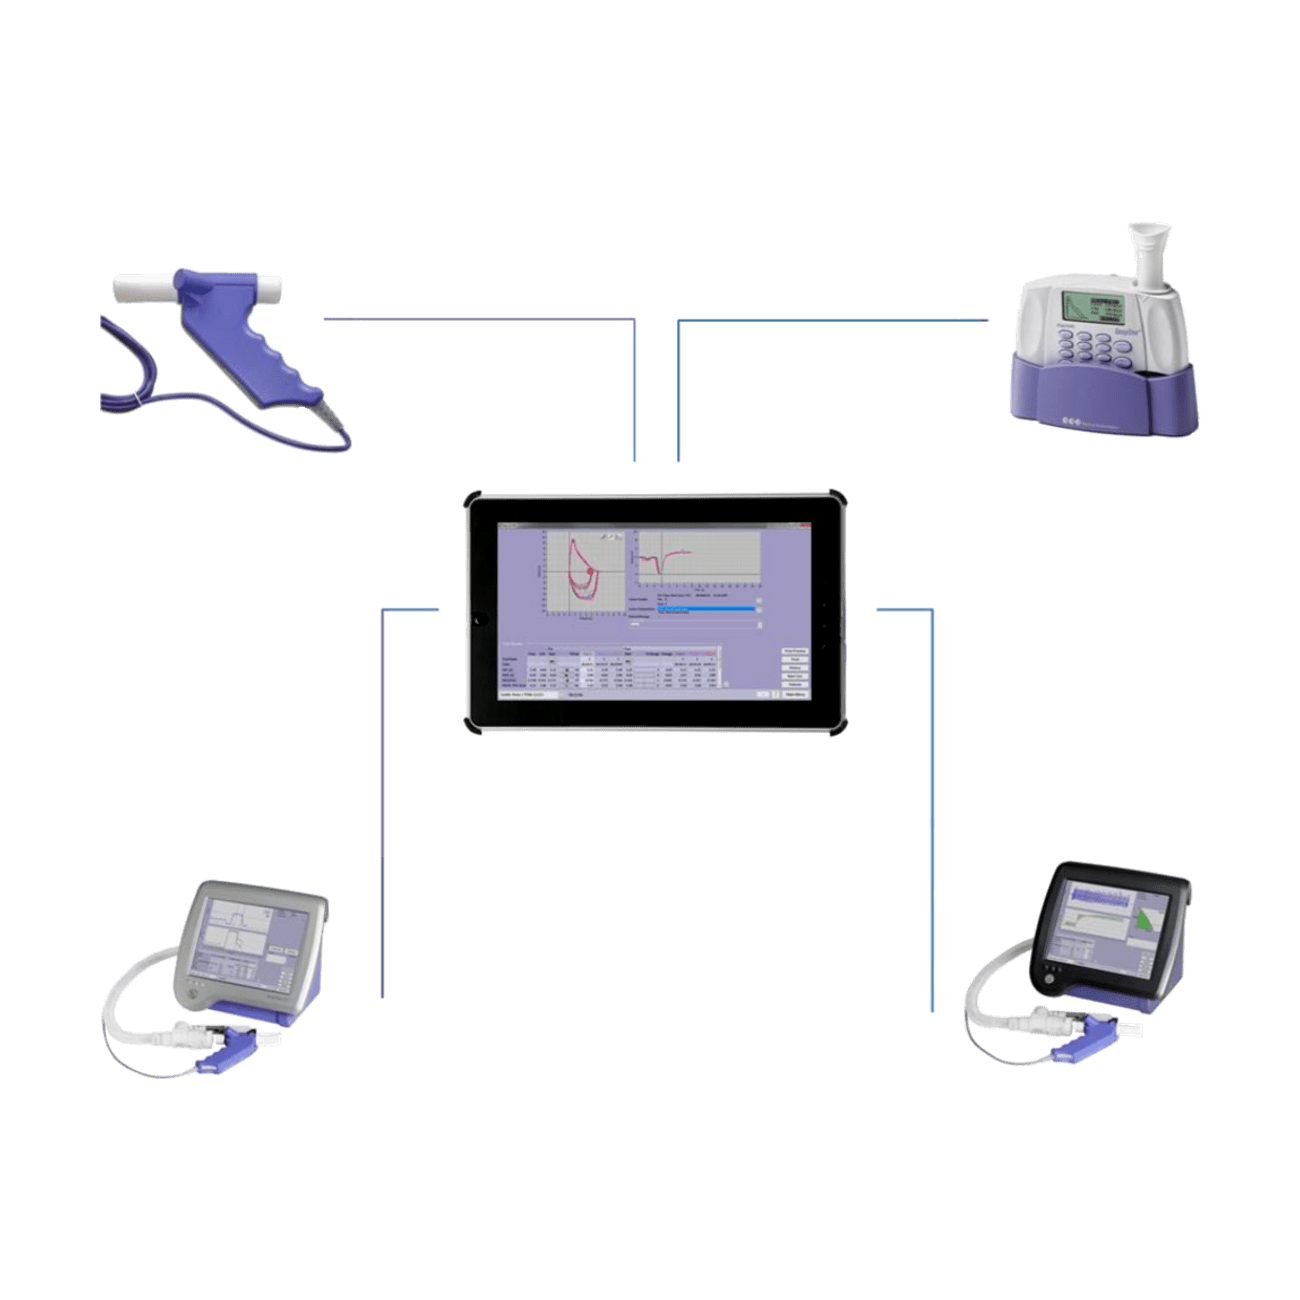

- lässt sich alleinig im Mobil-Modus, wie auch direkt in Verbindung mit einem PC verwenden

- Bluetooth und Anbindung an elektronische Patientenverwaltungssysteme (EMR)

- Datenaustausch über Bluetooth oder USB mit 'EasyOne Connect'-Software

- Einfache Verbindung zum PC für Echtzeit-Grafiken, Datenaustausch und Anbindungen

- Drucken über direkten USB-Anschluss oder via 'EasyOne Connect'